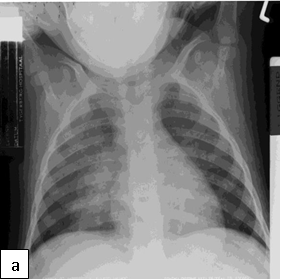

Chest x-ray is not usually diagnostic but may show bilateral diffuse parenchymal infiltrates with a “ground-glass” or reticulogranular appearance, but can be normal or have only mild parenchymal infiltrates. The earliest infiltrates are perihilar, progressing peripherally before reaching the apical portions of the lung.